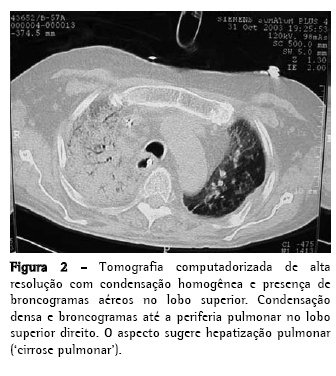

Homem, 56 anos, com diagnóstico de FPI (clínicofuncional-tomográfico-patológico) há cinco anos, evoluiu progressivamente com dispnéia a mínimos esforços e tosse mucóide escassa, intensa e de difícil controle. Apresentava, no mês do transplante pulmonar, hipoxemia e hipercapnia (PaO2 57 mmHg e pressão parcial de dióxido de carbono no sangue arterial 45 mmHg, em repouso e no ar ambiente ao nível do mar), DCO 29% do previsto, capacidade vital forçada 40,8% (1,41 L) e o volume expiratório forçado no primeiro segundo 52,6% (1,31 L). A cintilografia perfusional pulmonar demonstrava fluxo arterial de 76,7% para o pulmão direito e 23,3%, para o pulmão esquerdo. Os exames laboratoriais para o diagnóstico de doenças do colágeno e o inquérito epidemiológico para as doenças intersticiais conhecidas foram negativos. Durante os cinco anos de acompanhamento, tinha utilizado corticosteróides (prednisona 0,25 a 1 mg/kg/dia), imunossupressores (azatioprina ou ciclofosfamida 0,5 a 2 mg/kg/dia) e antifibrótico/imunomodulador (interferon-.1b) por quatro meses. O transplante foi unilateral à esquerda, correspondendo à menor perfusão arterial e maior intensidade do acometimento do interstício pela tomografia computadorizada de alta resolução (TCAR). No pós-operatório imediato evoluiu com instabilidade torácica devido à fratura de três arcos costais, em decorrência da tração de costelas osteopênicas durante o fechamento da ferida cirúrgica, e com isquemia de reperfusão pulmonar grave (relação PaO2/fração inspirada de oxigênio = 124). Permaneceu em ventilação mecânica (VM) invasiva por dez dias, traqueostomizado, e recuperando-se progressivamente da hipoxemia. O esquema de imunossupressão iniciado foi composto pela ciclosporina 5 mg/kg de 12/12 h, prednisona 0,5 mg/ kg/dia e azatioprina 2 mg/kg/dia, além do anticorpo anti-receptor da interleucina-2 basiliximab no 1º e 4º dias pós-operatório e da metilprednisolona 1 g no pré-operatório. Obteve alta da unidade de terapia intensiva para o quarto da unidade semi-intensiva, mas no 8º dia na unidade semiintensiva houve exacerbação da dispnéia, associada ao retorno da tosse seca e de progressiva estertoração crepitante em todo o hemitórax direito, sendo re-encaminhado para a unidade de terapia intensiva. Uma nova avaliação foi feita através de TCAR, broncofibroscopia com lavado broncoalveolar (LBA) e biópsia transbrônquica do lobo inferior esquerdo e do lobo superior direito. Todas as culturas foram negativas, o LBA tinha padrão neutrofílico, sem eosinófilos ou macrófagos com hemossiderina, e o histopatológico não foi conclusivo. Foi realizada arteriografia pulmonar e, posteriormente, vídeotoracoscopia com biópsia pulmonar em três diferentes regiões do lobo superior direito para assegurar a representatividade da doença (Figuras 1 e 2). A arteriografia não demonstrava doença tromboembólica.

As imagens radiográficas demonstravam condensação dos lobos médio, superior e inferior direito, e o diagnóstico estabelecido foi de exacerbação da FPI no pulmão nativo, caracterizado principalmente pelo aspecto histológico de PIU (infiltrado não-uniforme e multifocal, com espessamento inflamatório e fibroso do interstício alveolar, cistos pulmonares, fibrose peribronquiolar, hiperplasia alveolar e ausência de membranas hialinas) e pelas ausências de crescimento microbiano nos tecidos pulmonares e de descompensação cardiovascular. Sabe-se que na FPI, o pulmão se torna progressivamente colapsado, o que pode simular imagens de condensações pulmonares. A variante acelerada da FPI está sendo recentemente descrita e deve ter o seu diagnóstico caracterizado pela exclusão de outras causas de exacerbações. A literatura menciona, no transplante pulmonar unilateral, a progressão crônica da FPI no pulmão nativo, não havendo relatos de progressão aguda. Este é o primeiro caso da literatura nacional descrito como FPI na sua fase acelerada.